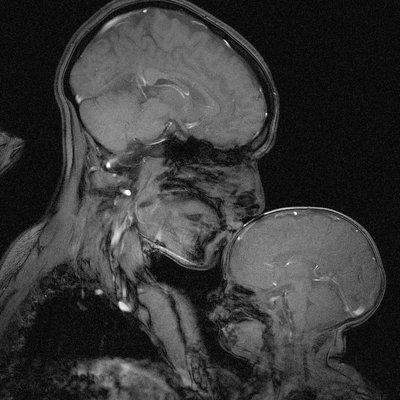

Rebecca Saxe

Rebecca Saxe is a cognitive neuroscientist at MIT, specializing in the study of brain function and cognition. Based in Canada, she contributes to advancing understanding in cognitive neuroscience through her research at a leading institution. Her work at MIT positions her among experts in the field of brain science.